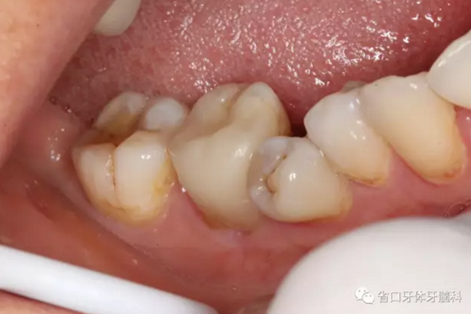

處置:46/清理髓腔,自酸蝕粘接,流動樹脂覆蓋根管口,牙體預備

圖3 牙體預備后,近中頰側(cè)牙體缺損平齊齦緣;近頰根管口流動樹脂覆蓋牙膠不足,下次改進

圖4 牙體預備后頰側(cè)觀